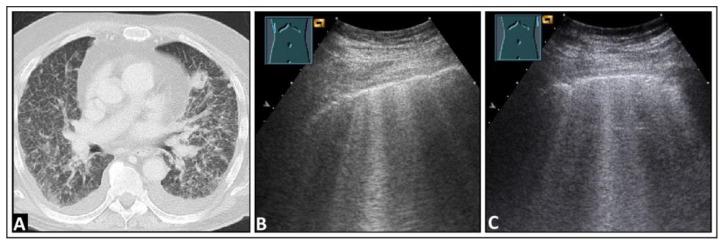

Lung ultrasound is a well-established diagnostic approach used in detecting pathological changes near the pleura of the lung. At the acoustic boundary of the lung surface, it is necessary to differentiate between the primary visualization of pleural parenchymal pathologies and the appearance of secondary artifacts when sound waves enter the lung or are reflected at the visceral pleura. The aims of this pictorial essay are to demonstrate the sonographic patterns of various pleural interface artifacts and to illustrate the limitations and pitfalls of the use of ultrasound findings in diagnosing any underlying pathology.

肺部超声是一种成熟的诊断方法,用于检测肺胸膜附近的病理变化。在肺表面的声学边界处,当声波进入肺部或在内脏胸膜处反射时,有必要区分胸膜实质病变的主要可视化表现和继发性伪像的外观。这篇图文并茂的文章旨在展示各种胸膜界面伪像的超声图像模式,并说明在诊断任何潜在病理时使用超声检查结果的局限性和陷阱。